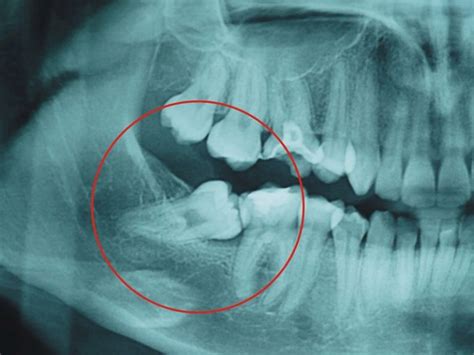

Las muelas del juicio pueden estar incluidas, es decir, totalmente cubiertas por la encía, lo que puede generar infecciones, quistes o daño en las raíces de los molares vecinos. En otros casos, las muelas están parcialmente erupcionadas, lo que suele provocar episodios recurrentes de infecciones y problemas periodontales debido a la acumulación de bacterias. Cuando estas muelas presentan caries, salvo en situaciones concretas, no se suelen realizar empastes y se prescribe su extracción.

- Muelas del juicio retenidas: Estas quedan completamente ocultas dentro de las encías. Pueden provocar infecciones, dañar las raíces o los huesos de las piezas dentales adyacentes, e incluso generar quistes o tumores en casos excepcionales.

Las radiografías, revelan la posición y el desarrollo de las muelas del juicio, permitiendo identificar si estas se encuentran impactadas, es decir, si no tienen espacio para erupcionar correctamente. Adicionalmente, el ortodoncista analiza la mordida del paciente y el espacio disponible en la boca para determinar si las muelas del juicio podrían generar apiñamiento, desplazamiento o daño en los dientes adyacentes.